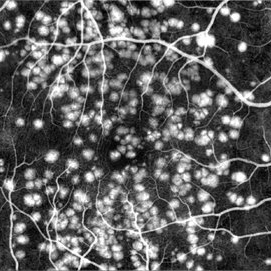

A 32-year-old female patient attended the Suel Abujamra Institute (ISA) for evaluation and management. In the process of evaluating the visual picture, important retinal alterations, typically of diabetic retinopathy, were observed. As shown in the OCT-A (Angioplex) exam, extensive area of ischemic vascular incompentence.

Photographer: JEFFERSON R SOUSA - Centro de Estudos e Pesquisas Oftalmológicas Dr. Andre MV Gomes, Instituto Dr. Suel Abujamra São Paulo-Brasil

Imaging device: Angioplex protocol, OCT CIRRUS 5000. Zeiss

Condition/keywords: diabetic mellitus, diabetic retinopathy, ischaemic diabetic maculopathy, ischemia, ocular ischemic syndrome, retinopathy